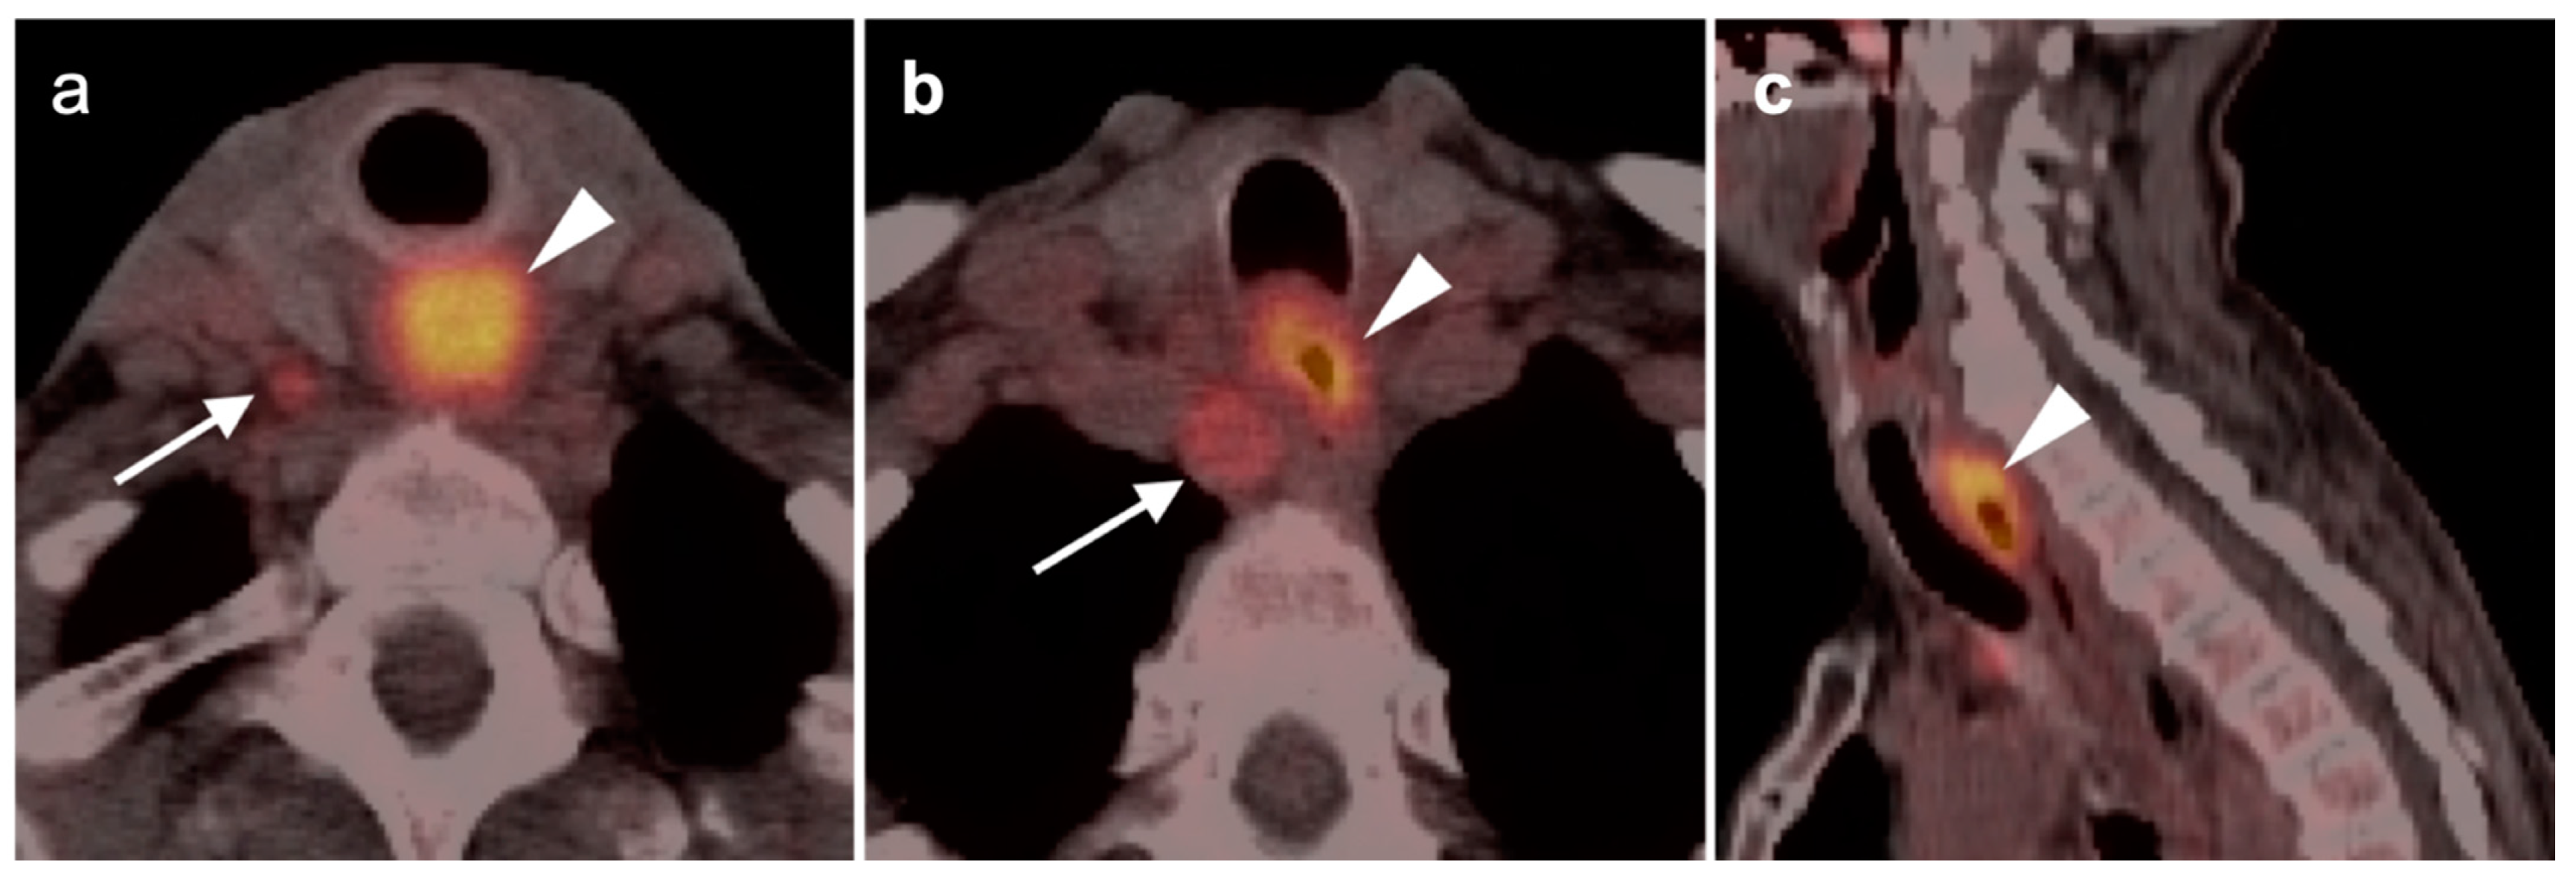

2.6. Thyroid Cancer

- Medullary thyroid cancer